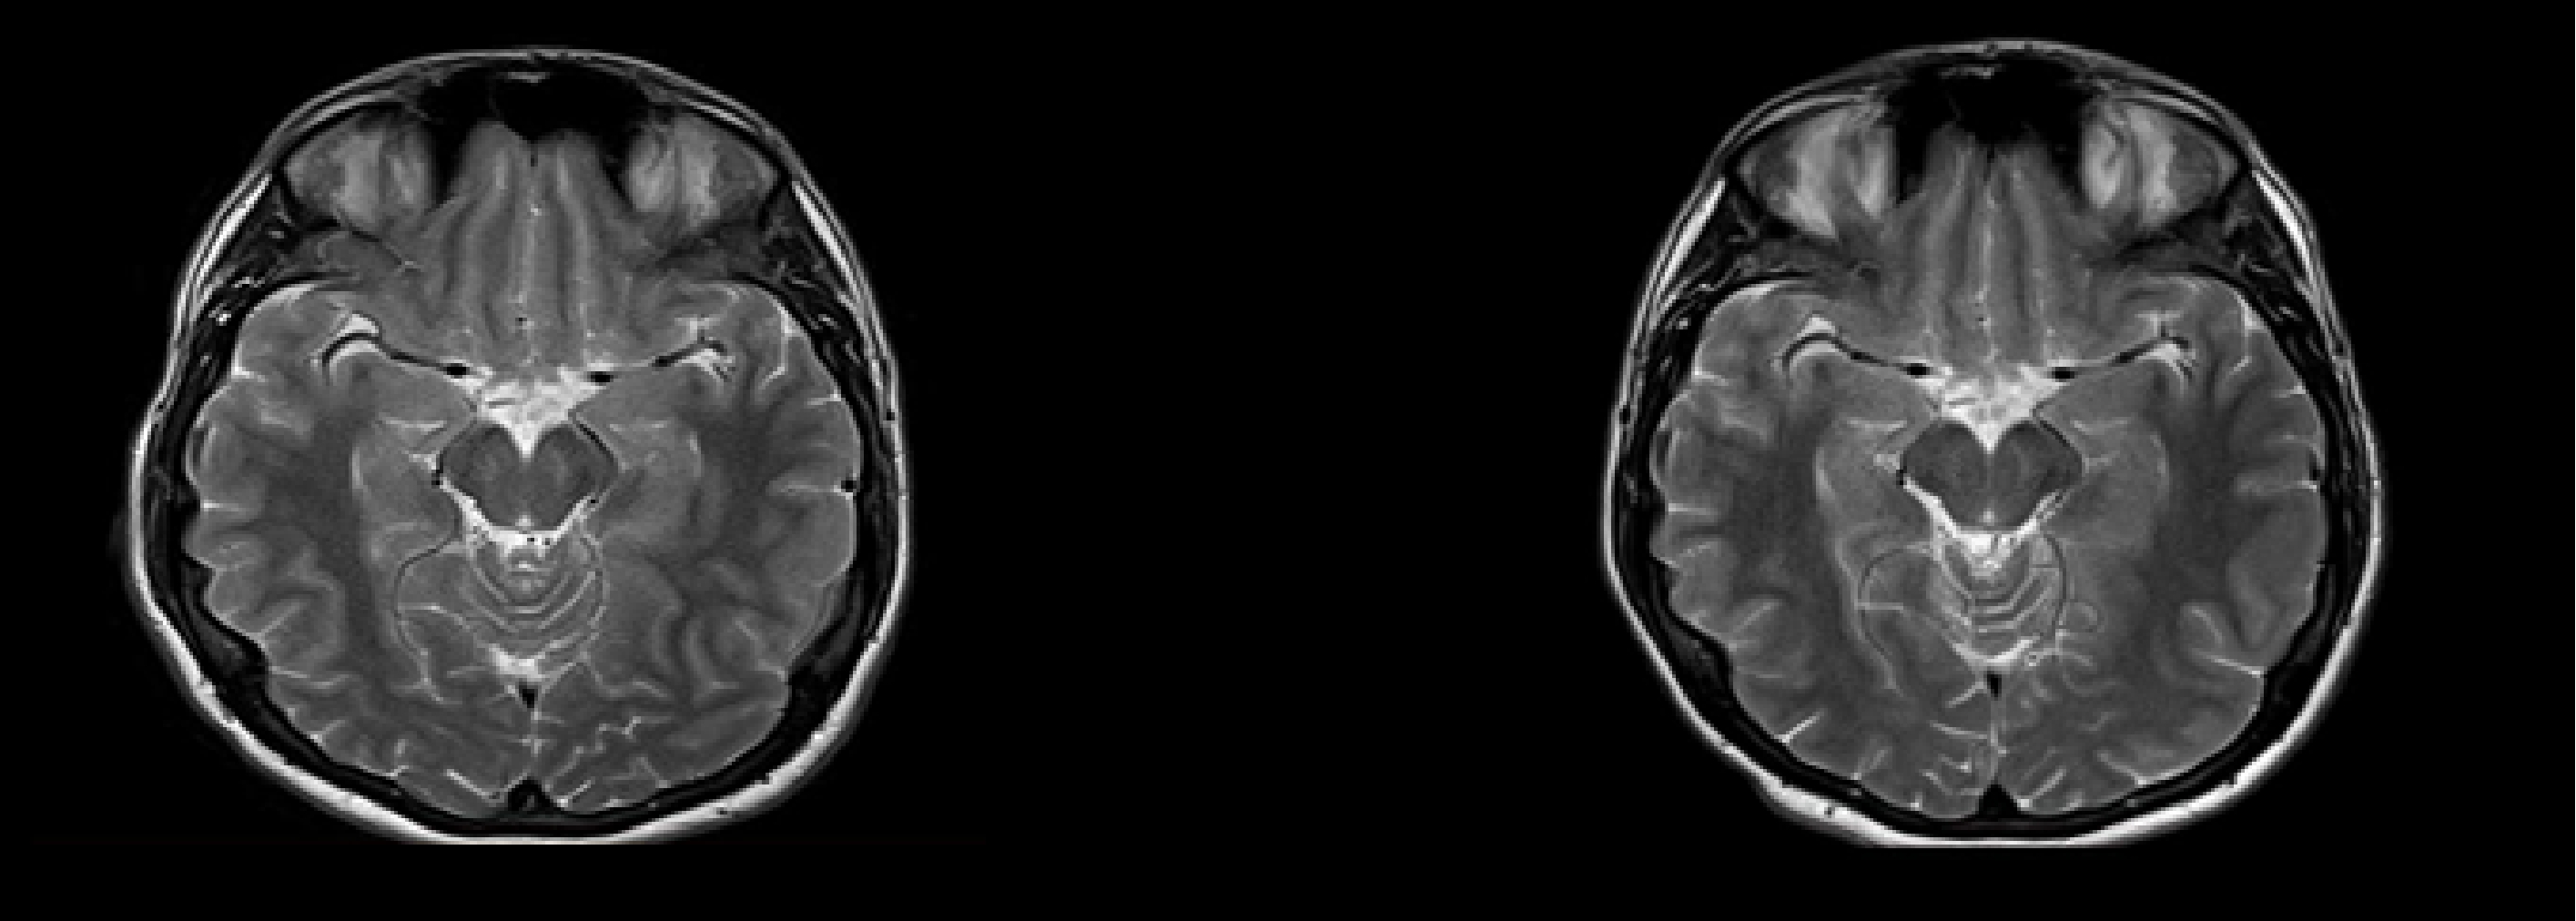

1.5T磁振造影掃描儀

特別引進德國西門子高階機種,快速、精確、解析度高,針對腦部脊髓神經系統、脊椎、骨骼關節肌肉、腹部、骨盆腔實質器官性乳房系統、生殖系統等,皆能達到準確診斷的效果。

磁振造影(Magnetic Resonance Imaging ,MRI)是運用RF射頻波激發體內水、脂肪中的氫原子,使其產生共振,進而產生不同強度的信號所製造出的影像,輔以電腦影像處理,呈現人體內部立體斷層切片影像。

腦部磁振造影 (無顯影劑) |

以無輻射之磁振造影評估腦部組織是否萎縮、退化、梗塞等。 |

以無輻射之磁振造影評估腦部腫瘤及腦血管梗塞等。 |